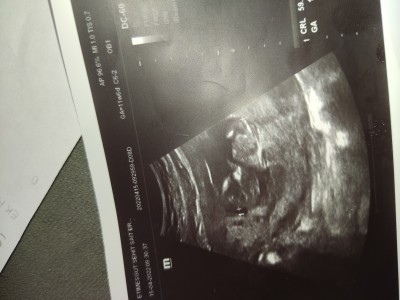

Merhabalar , cinsiyet tahmini yapanlar bakabilir mi.

NT ; 1.3 ÇIKTI sanırım normal :)

Gebelik haftası 12+3

Burda daha net görünüyor

Canım. Hiçbir şey anlaşılmıyor. Anlaşılsa doktor söylerdi zaten haftan küçük daha bir ay sonra kesinleşir inşallah. Hayırlı olsun.

Doktorum tahmin etti, bilenler oluyor bakıp onlar için attım :))  ayrıca küçük değil henüz belli heryeri ve anlaşılıyor